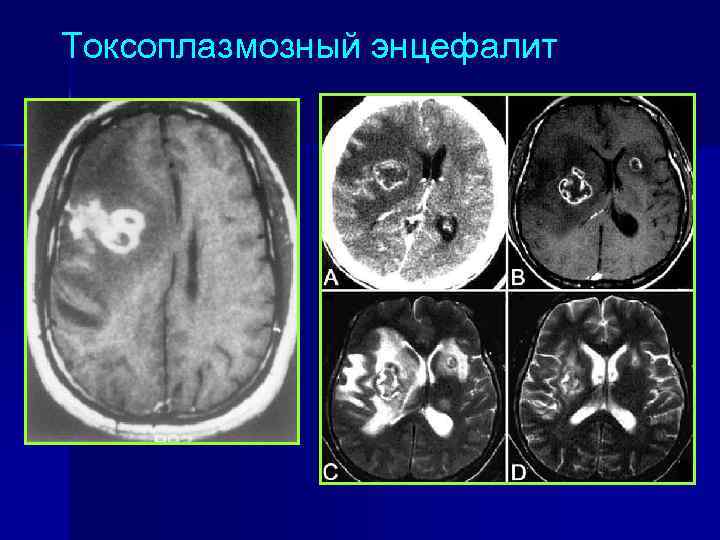

Оппортунистические поражения НС у ВИЧ-инфицированных Токсоплазмозный энцефалит n Туберкулезный менингит n Криптококковый менингит n Цитомегаловирусный энцефалит / миелит n Энцефалит, вызванный ВПГ, VZV n Прогрессирующая мультифокальная лейкоэнцефалопатия (вирус JC) n Первичная лимфома ЦНС n

Токсоплазмозный энцефалит